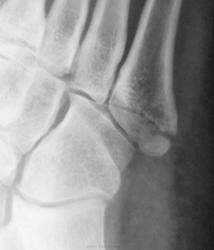

Травма.  Пациент направлен на рентгенографию стопы.

Может и в одиночестве, но ногу подвернул здорово. А перелом-то классический.

А мне не понравилась головка 2 плюсневой кости - уплощена, без видимых признаков перелома. Похоже на последствие остеохондропатии Келера?